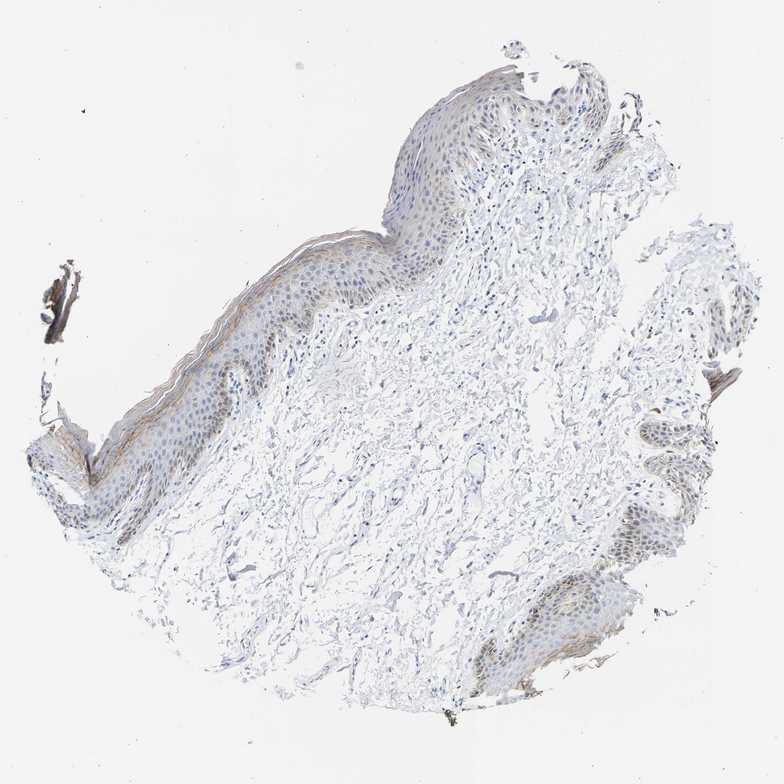

SKIN 1 - Antibody stainingi

Antibody staining in the annotated cell types in the current human tissue is reported as not detected, low, medium, or high, based on conventional immunohistochemistry profiling in selected tissues. This score is based on the combination of the staining intensity and fraction of stained cells.

Each image is clickable and will lead to virtual microscopy that enables deeper exploration of all samples and also displays staining intensity scores, fraction scores and subcellular localization as well as patient and tissue information for each sample.

Antibody HPA026813Antibody CAB020824

Langerhans Not detectedNot detected

Fibroblasts Not detectedNot detected

Keratinocytes LowNot detected

Melanocytes LowNot detected